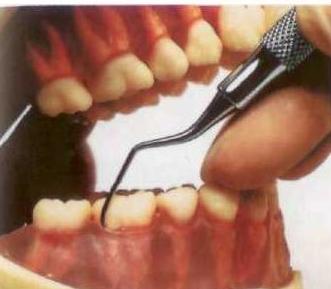

Рис. 8. Профессиональная гигиена

Если вовремя не удалять зубной камень, он будет травмировать ткани периодонта. А главное — камень способствует накоплению зубного налета, являясь хорошим ретенционным пунктом.

Профессиональная гигиена (рис. 8) подразумевает удаление зубного налета и камня стоматологом с помощью специальных ручных инструментов или ультразвука, а также полировку зубов с помощью специальных щеточек и резинок с пастами, содержащими абразивы. Эта процедура рекомендуется всем пациентам не реже одного раза в шесть месяцев, а в некоторых случаях (например, при заболеваниях периодонта) и чаще.